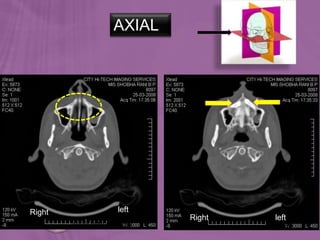

AXIAL

SAGITTAL

CORONAL

To acquire a volume of data, 2 scanning modes are

possible-

1) SEQUENTIAL – the table with the patient is

positioned and the attenuation data are acquired.

Then the table is moved to a next position, and a new

acquisition is made.

2) SPIRAL – the table moves from the initial position

to the end position while the X-Ray attenuation data

are acquired.

Ortho radio diagnosis

Right left